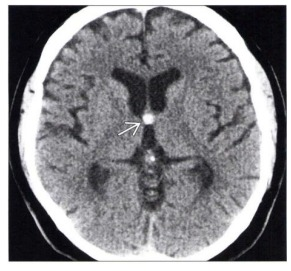

Tomografia do crânio sem contraste em corte axial ao nível do forame de Monro demonstra a imagem apontada pela seta na figura abaixo. O diagnóstico CORRETO é: